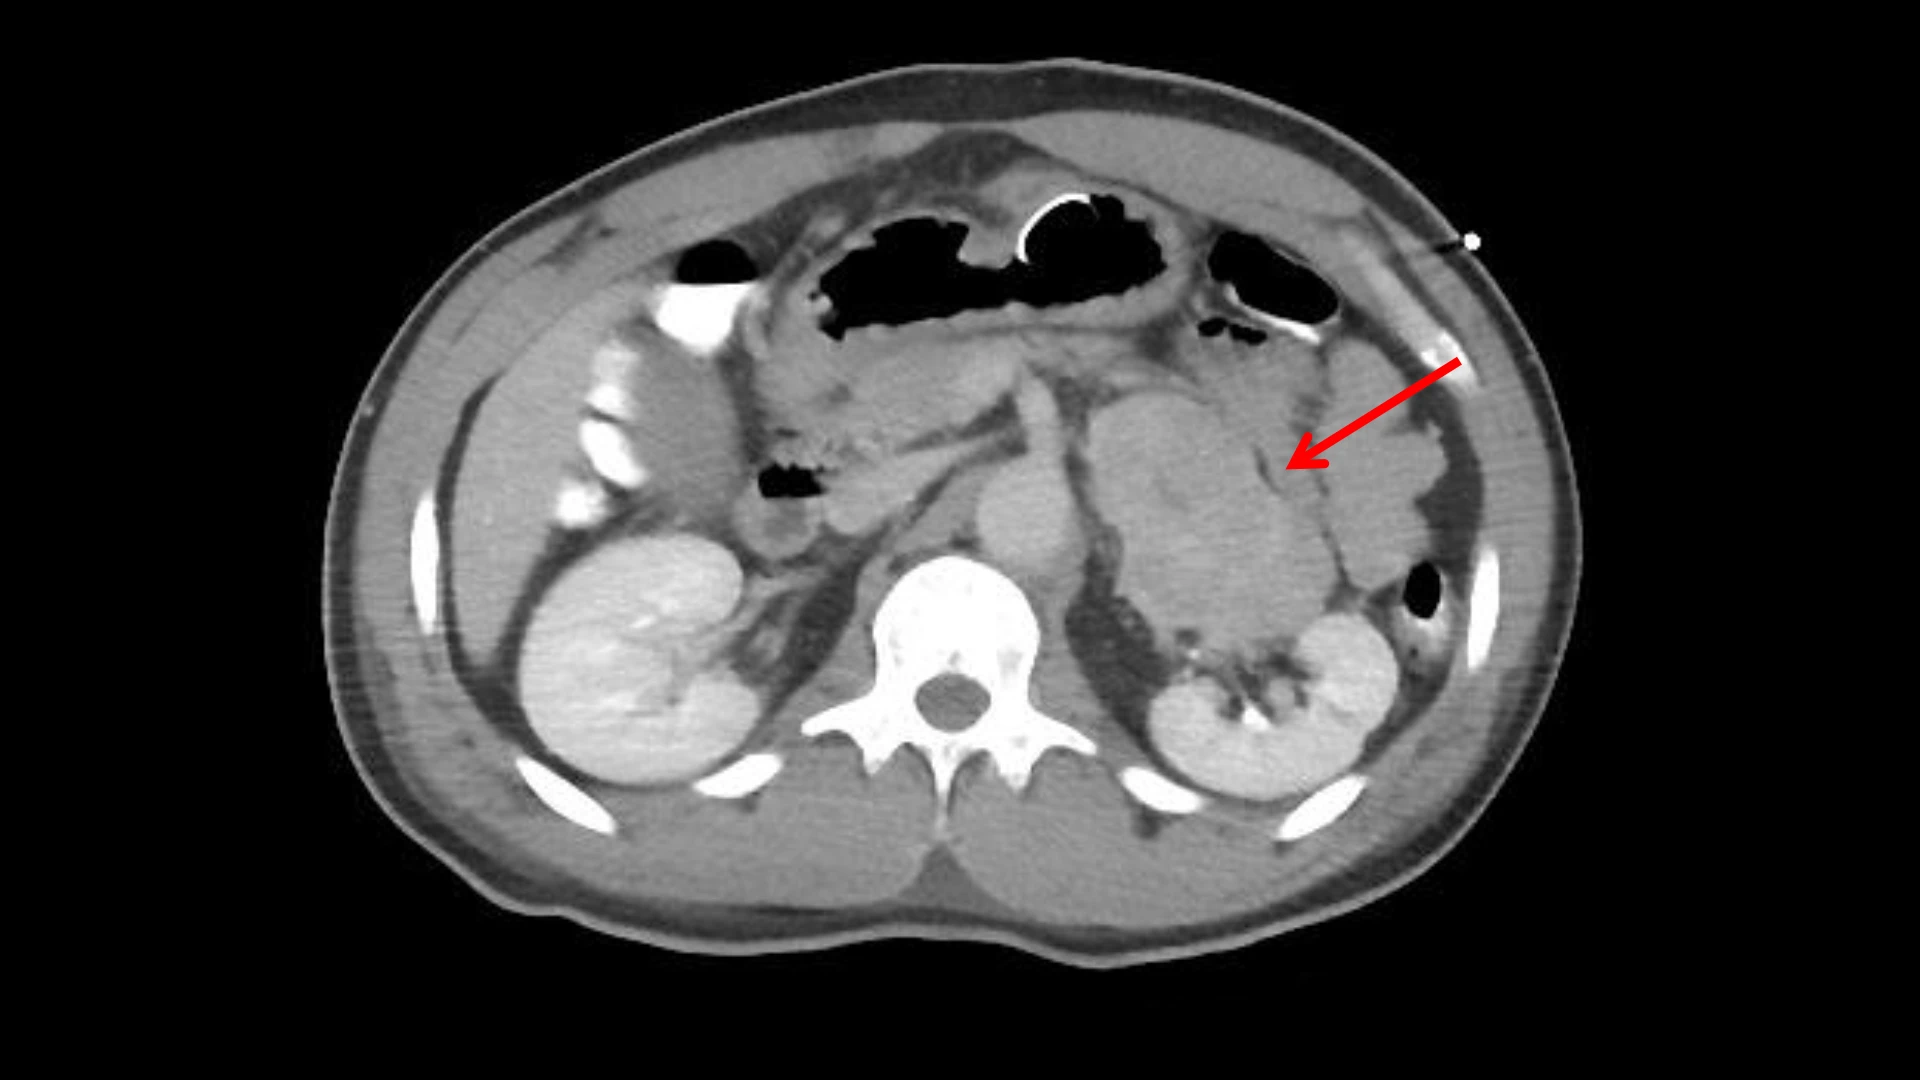

Adrenocortical carcinoma is adjacent to the left kidney on the CT image.